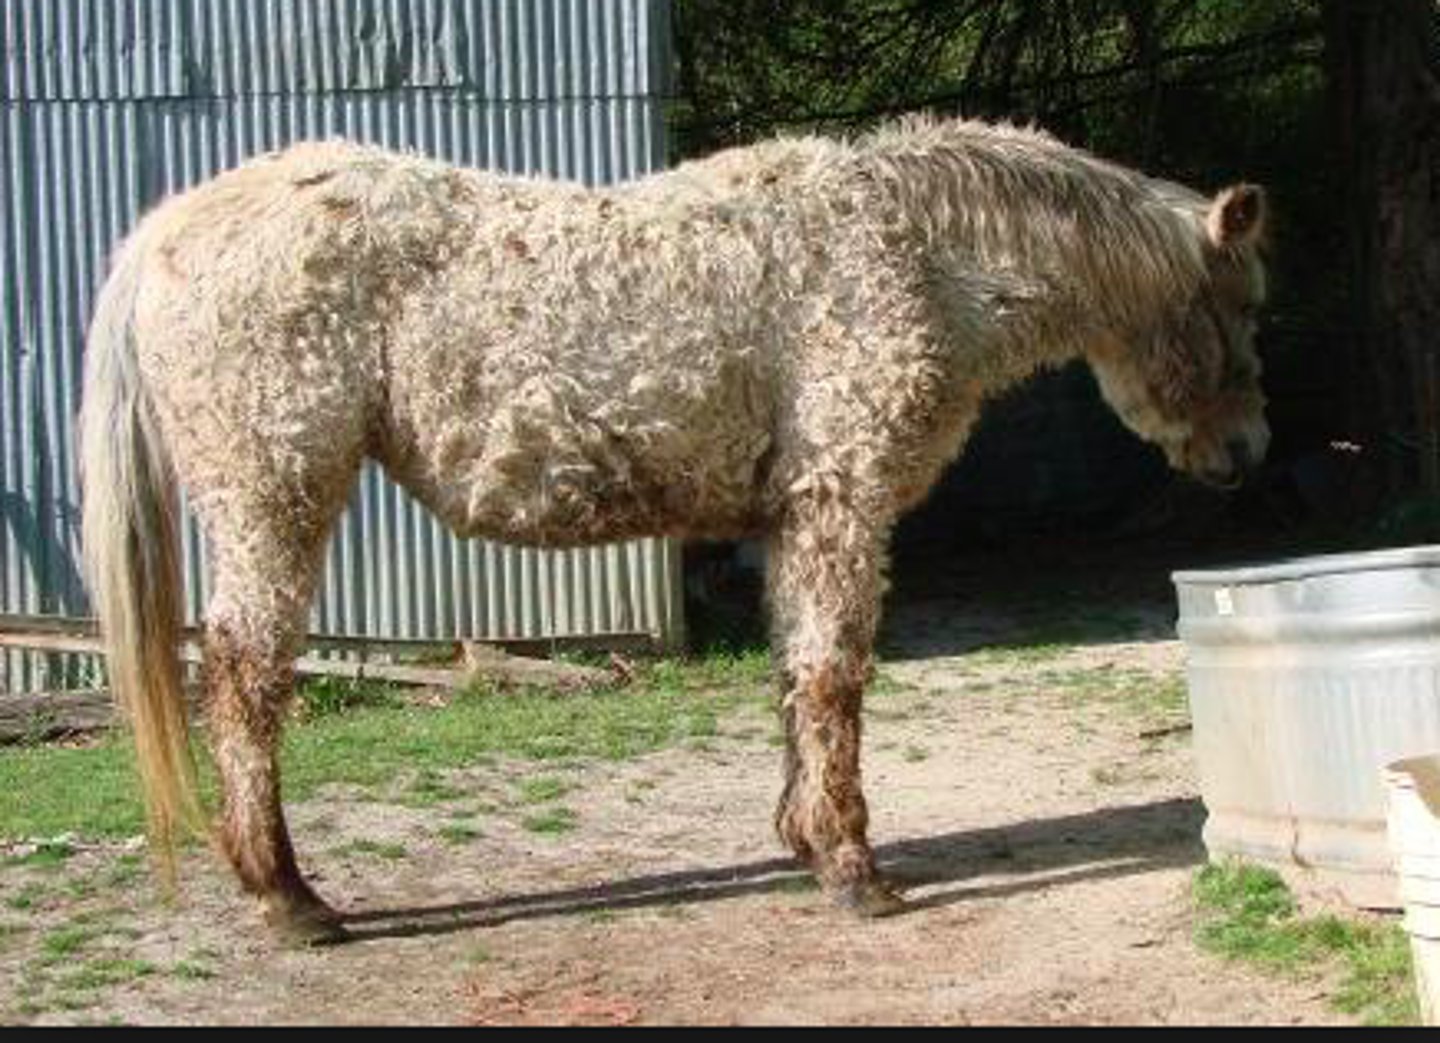

hypertrikose (hirsutisme)= lang irregular pels pga. manglende fældning

Hypertrikose, hvor der ofte ses neoplasi i hypofysen

Hest, hvad er den patoanatomiske diagnose?